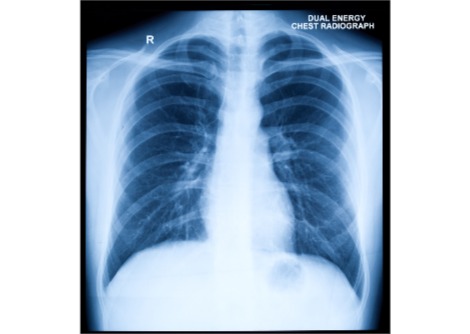

لكن عمليات زراعة كبد الخنازير تُشكل تحديًا خاصًا، كما قال وانغ: "الكبد معقد للغاية". فعلى عكس القلب الذي يضخ الدم والكلى التي تُنتج البول، يتميز الكبد بقدرة فائقة على الإنجاز. يقوم هذا العضو المفصص بالعديد من الوظائف، بما في ذلك إزالة السموم من الدم، وإنتاج العصارة الصفراوية للمساعدة في الهضم، والتخلص من خلايا الدم الحمراء القديمة، وتخزين الطاقة، وإنتاج جزيئات تساعد على تخثر الدم.

يقول آدم غريسمر، جراح زراعة الكبد في مركز لانغون الصحي بجامعة نيويورك، إن نجاح زراعة عضو خنزيري في أداء جميع هذه الأدوار سيكون صعبًا للغاية. ويضيف أن الوظائف التي يؤديها الكبد حيوية للغاية لأجسامنا. وإذا كان هناك أي اختلاف ولو طفيف بين كيفية عمل أعضاء الخنزير والبشر، "فأعتقد أننا سنواجه مشاكل".